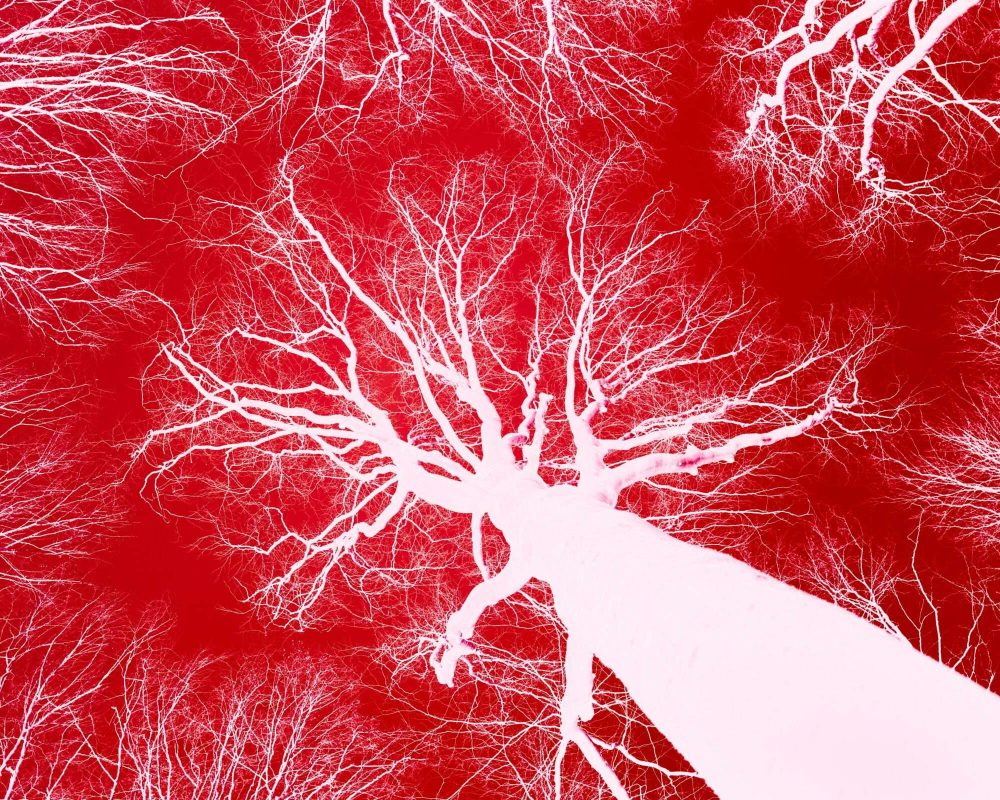

Szív- és érrendszer

Az édes üröm (Artemisia annua) hatóanyaga nemcsak a fertőző és daganatos betegségekkel kapcsolatban került a kutatások középpontjába, hanem a szív- és érrendszer egészségének támogatása terén is ígéretesnek bizonyult. A kardiovaszkuláris betegségek világszerte vezető haláloknak számítanak, és kialakulásuk hátterében gyakran az oxidatív stressz, a krónikus gyulladás, a magas vérnyomás és az érelmeszesedés áll. Kutatások szerint az egyik legfontosabb tulajdonsága lehet, hogy csökkentheti a szabad gyökök okozta oxidatív stresszt, amely az érfalak károsodásának és az érelmeszesedés kialakulásának egyik fő hajtóereje. Laboratóriumi vizsgálatok arra is utalnak, hogy mérsékelhet egy olyan sejten belüli folyamatot, amely a gyulladásért felelős anyagok termelődését indítja el. Ennek hatására csökkenhet az érfal gyulladása, lassulhat a plakkok képződése, és mérséklődhet a szövetkárosodás. Állatkísérletekben megfigyelték, hogy hozzájárulhat az endotél (az erek belső falának) működésének javításához, amely alapvető a vérkeringés szabályozásában. Mivel az endotél-diszfunkció a magas vérnyomás és a szív-érrendszeri betegségek egyik legkorábbi jele, ez a kedvező hatás különösen ígéretes lehet. Egyes kutatások értágító hatást is jeleztek, ami hozzájárulhat a vérnyomás szabályozásához. Kedvező eredményeket tapasztaltak a szívizom védelmével kapcsolatban is. Oxigénhiányos állapotok után a növényből kivont hatóanyag kísérletes környezetben mérsékelte a sejtkárosodást, és csökkentette a reperfúziós sérülést, vagyis azt a károsodást, amely a vérkeringés helyreállításakor jelentkezhet. Ez arra utal, hogy hatóanyaga hozzájárulhat a szívizom életképességének megőrzéséhez kritikus helyzetekben. A koleszterin- és lipidanyagcserére gyakorolt hatásai is biztatók. Több kísérletben a növény hatóanyaga csökkentette az LDL-koleszterin és a trigliceridek szintjét, miközben növelte a védő HDL-koleszterin mennyiségét. Ez kedvező lehet az érelmeszesedéssel összefüggő folyamatok szempontjából, és hozzájárulhat a szív- és érrendszeri egészség megőrzéséhez.